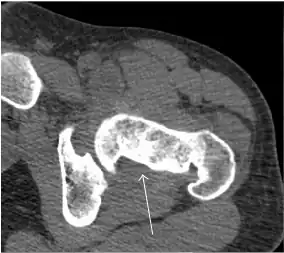

Synovial chondromatosis can be confidently diagnosed by X-ray when calcified cartilaginous chondromas are seen. However, other synovial proliferative processes, such as pigmented villonodular synovitis, require MRI for accurate diagnosis, although noncalcified synovitis can be suspected in radiographs by indirect signs, such as soft tissue swelling and/or erosions in the femoral head, femoral neck, or acetabulum (Figure 7).[1]

Figure 7:

Axial CT image of pigmented villonodular synovitis eroding the posterior cortex of the femoral neck.[1]

In synovial proliferative disorders, MRI demonstrates synovial hypertrophy. In the case of PVNS, characteristic foci of low signal intensity related to hemosiderin deposition are better seen on gradient echo T2* images (Figure 7). In the case of synovial osteochondromatosis, the synovial hypertrophy is accompanied by intermediate signal cartilaginous loose bodies and/or low signal calcified loose bodies.[1]